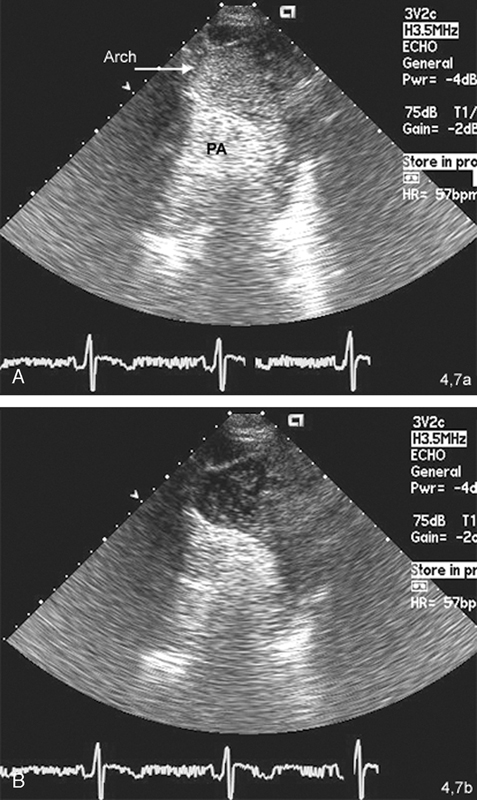

فحوصات تشخيصية لبعض امراض القلب والشرايين التاجية